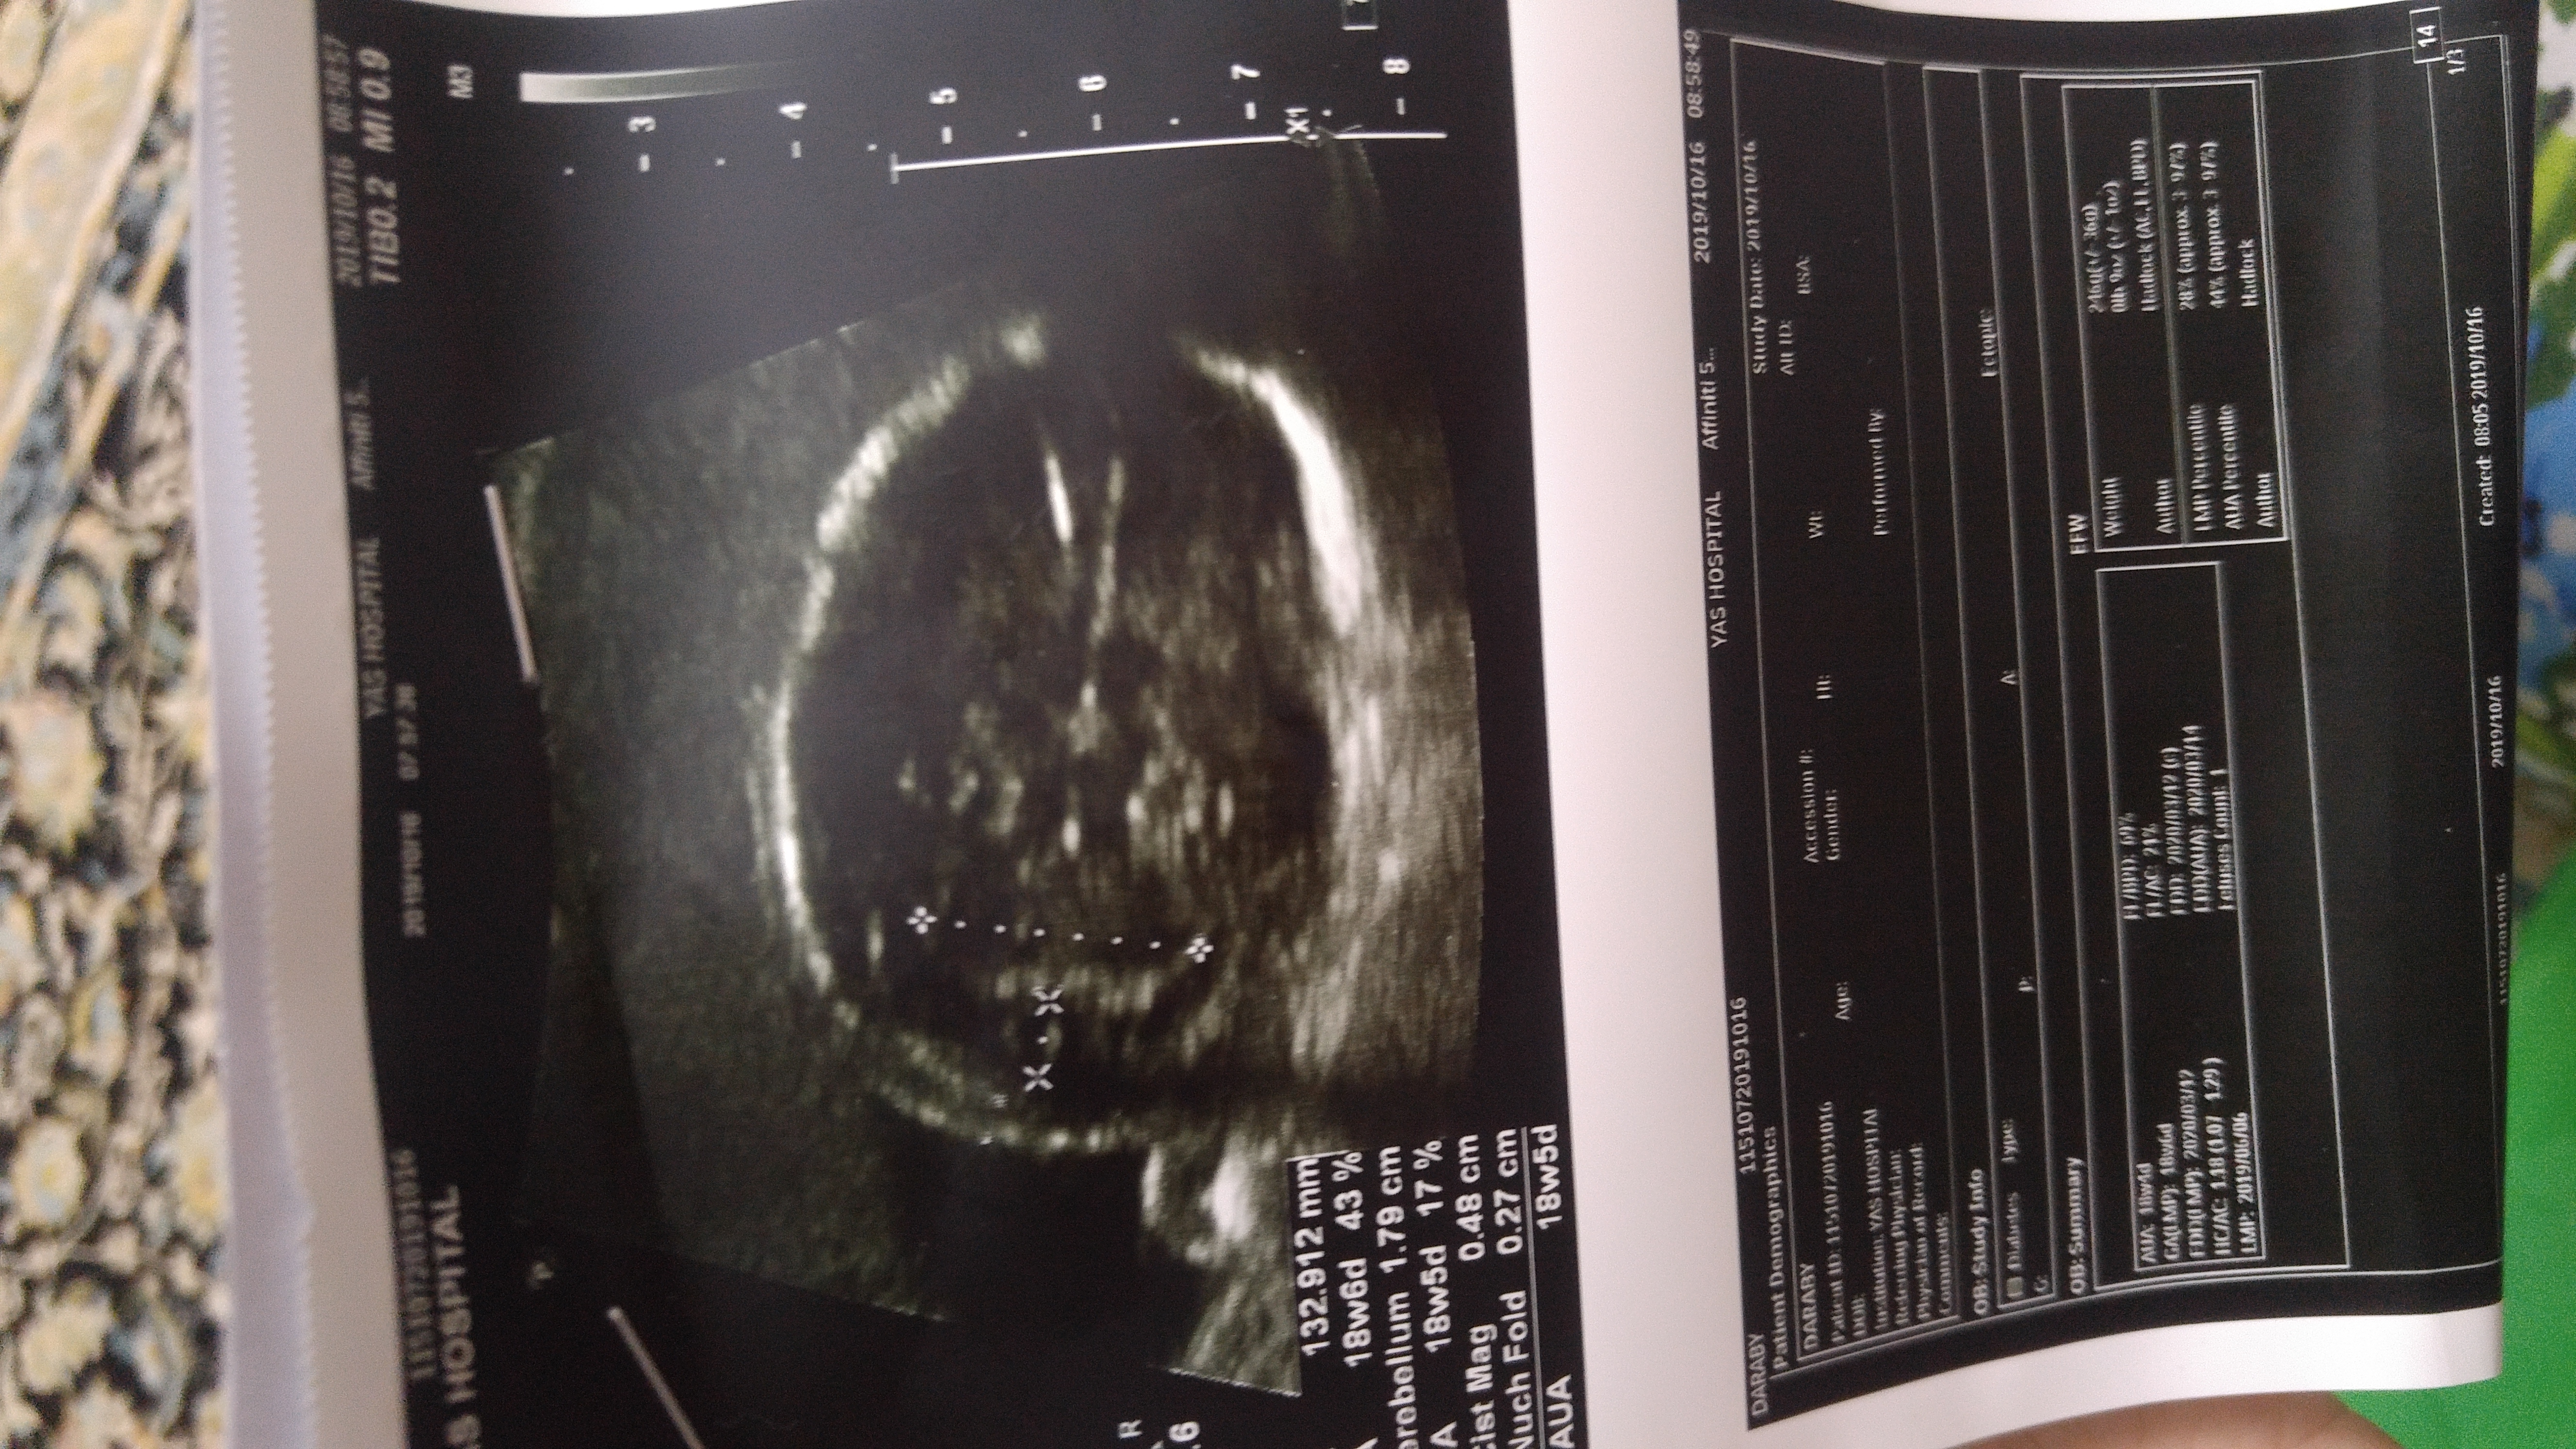

هفته 20 ...4 روز پیش رفتم سونو

نه اصلا عکس واضح ندارم ازش....چندتا دادن نمیدونم چی به چیه

اینابودن نمیدونم اوکی هست یا نه

انومالی قطعیه جنسیت چون اجزا به اجزا اسکن میکنن